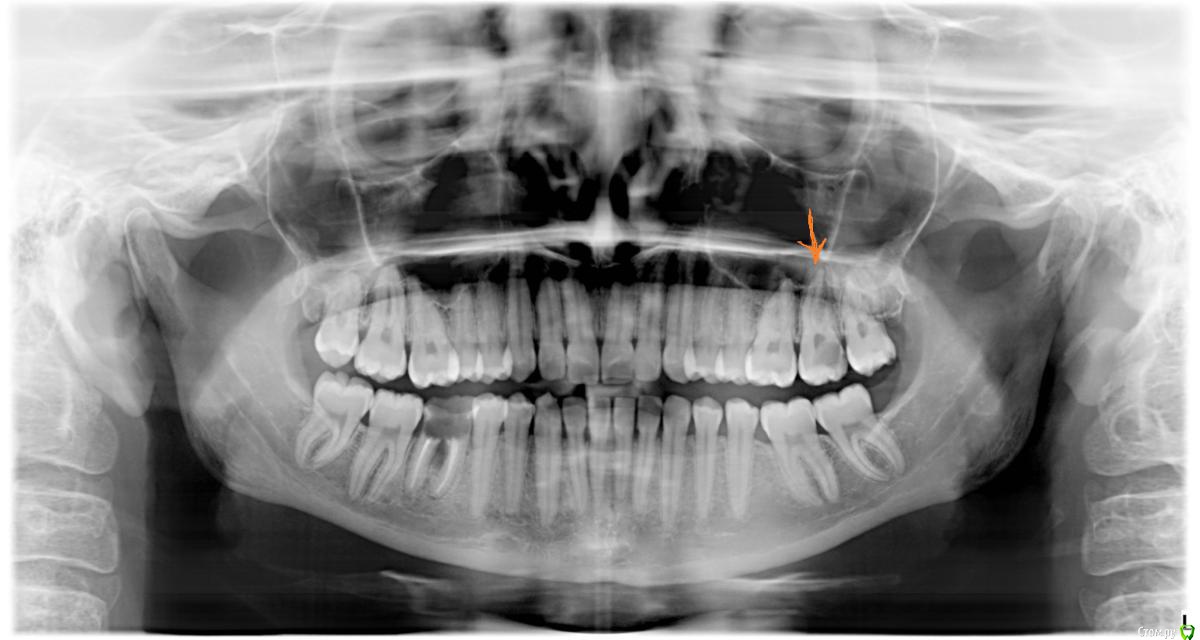

Оксана1318 Опубликовано 23 декабря, 2016 Поделиться Опубликовано 23 декабря, 2016 (изменено) Доброго времени суток! Подскажите, пожалуйста, какое лечение подойдет для зуба, над которым стрелка оранжевая на снимке (на снимке правая сторона сверху). Недели две назад болел, потом прошел, сейчас начинает болеть, только если не почистить зубы через час после еды (а именно реагирует на сладкое, крупы, иногда хлеб). На холодное и горячее появляется неприятные ощущения, но невысокой интенсивности. Врач сказал, что пульпит и полость кариозная большая (на снимке видно). Периодонтит под вопросом. Часть зуба отколота сбоку. Рекомендация первого врача - керамическая накладка. Подойдет она сюда? Какой риск, если поставить пломбу ? Другой врач назначил коронку, но я склоняюсь к накладке. Подскажите, как будет лучше в данной ситуации ?Заранее спасибо.Снимок прилагается. Изменено 23 декабря, 2016 пользователем Оксана1318 Ссылка на комментарий

AndyAndy Опубликовано 23 декабря, 2016 Поделиться Опубликовано 23 декабря, 2016 Судя по снимку, для накладки условия не очень хорошие: глубокое разрушение тканей зуба скорее всего под десну, а также обширное разрушение. Своих твёрдых тканей мало останется. Ссылка на комментарий

DmitrySH Опубликовано 23 декабря, 2016 Поделиться Опубликовано 23 декабря, 2016 Хороший вариант, но восьмой зуб надо убрать 1 Ссылка на комментарий

M@estro Опубликовано 23 декабря, 2016 Поделиться Опубликовано 23 декабря, 2016 (изменено) Спасибо за ответ! Да, восьмые уберут. Керамическая вкладка- хороший вариант ? Скажите, а остатки моего зуба не разрушатся от времени в таком случае ? Добрый вечер. Если все сделать грамотно - то вряд ли тканям что-то угрожает больше, нежели при протезировании коронкой. Главное - хорошо пролечить каналы, чтобы не пришлось к этому вопросу возвращаться вновь. P.S. Зуб справа на нижней челюсти - на удаление и имплантацию Изменено 23 декабря, 2016 пользователем M@estro 1 Ссылка на комментарий

DmitrySH Опубликовано 23 декабря, 2016 Поделиться Опубликовано 23 декабря, 2016 Спасибо за ответ! Да, восьмые уберут. Керамическая вкладка- хороший вариант ? Скажите, а остатки моего зуба не разрушатся от времени в таком случае ? Единственное чего мы не знаем, так это сколько тканей зуба останется после лечения. Если все сделано грамотно, то нет, в ближайшее время не разрушится зуб. Считайте это промежуточным этапом, между пломбой и коронкой. 1 Ссылка на комментарий